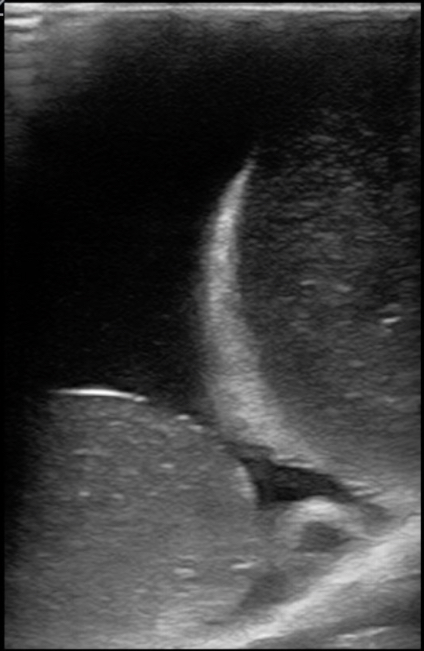

Figure 13. A model with normal testicle, large epididymis, and an epididymal cyst.